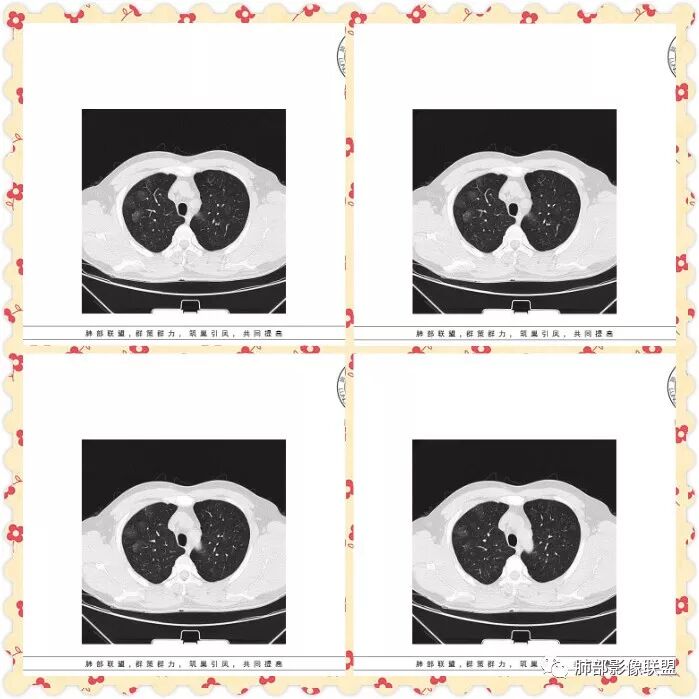

双肺多发磨玻璃影,大部分中央可见增粗血管影,部分血管边缘模糊破坏,左侧肩胛骨骨质破坏,周围巨大软组织肿块,软组织肿块内可见坏死及肿瘤骨,考虑肩胛骨骨肉瘤并双肺多发转移(点晕征)。

中年男性47岁。左侧肩胛骨骨质破坏并不规则状软组织密度影,与周围肌肉组织界限欠清。双肺内多发类圆形pggo,部分中间见血管,考虑左侧肩胛部恶性病变肺内血性转移。

管洪林:

男性,67岁,咳嗽痰中带血,左背部肿块,双肺弥漫可见磨玻璃结节,部分清晰,部分边缘模糊,部分其内可见明显点晕征,纵隔内无明显肿大淋巴结,左肩胛骨溶骨性破坏,临近明显软组织肿块,考虑左侧肩胛骨恶性肿瘤并双肺多发转移,点晕征提示血管来源。

病例分析:双肺多发磨玻璃影,部分磨玻璃影内可见点状实性结节,呈点晕征,边缘较散,模糊不清,左侧肩胛骨溶骨性骨质破坏,周围肌肉散在钙化,包绕骨质生长,综合考虑:左肩胛骨骨肉瘤伴双肺转移,其它(血管炎,多发血管瘤)

男性47岁。左侧肩胛骨骨质破坏并巨大软组织肿胀影,与周围肌肉组织界限欠清。双肺内多发圆形晕征,边缘清晰,点晕征。考虑左肩胛部恶性病变肺内血性转移,浆细胞瘤,骨肉瘤,黑色素瘤。

双肺多发磨玻璃影,部分边界清楚,部分边缘模糊,沿血管走行,其内血管明显增粗,部分磨玻璃影内可见点状实性结节,呈点晕征,左侧肩胛骨溶骨性骨质破坏,伴软组织块形成,可见少许残存骨化影,综合考虑:左肩胛骨骨肉瘤伴双肺转移,其内不出外血管炎

左侧肩胛骨溶骨性骨质破坏,伴软组织块形成,可见少许残存骨化影,双肺多发磨玻璃影,其内可见粗大血管影,部分呈点晕征,考虑:左肩胛骨骨肉瘤伴双肺转移

中年男性,咯血,双肺多发结节状、斑片状磨玻璃影,大部分中央可见增粗血管影,部分结节内见点征。左侧肩胛骨融骨性破坏并周围巨大软组织肿块,内见肿瘤骨,考虑肩胛骨骨肉瘤并双肺多发转移,均为转移瘤待排

47岁男性,咳血痰左肩背痛1月余,左肩胛骨破坏,破坏处及周边见软组织肿块,左肩胛区包块并皮肤破损,破损处无渗液、无脓不支持结核。两肺见多发磨玻璃影,沿血管走行,其内血管明显增粗,部分磨玻璃影内可见点状实性结节,呈点晕征,各磨玻璃影形态密度基本一致,提示同一来源,支气管未见明显增厚扩张——不支持气道来源。小叶间隔无增厚及纵隔未见明显肿大淋巴结——感觉淋巴瘤可能性较小。胸腹部皮肤散在红斑。整体考虑左肩胛骨恶性肿瘤并两肺转移。

quanyou:

1.双肺多发磨玻璃结节影,边界可分辨,病灶中央都可见一实性密度小结节影,注意不是钙化。这些病灶形态及密度是如此相似,宛如身着厚厚一层晕影蜉蝣深海之中,称之为“点晕征”。

注意:多发、点、厚晕